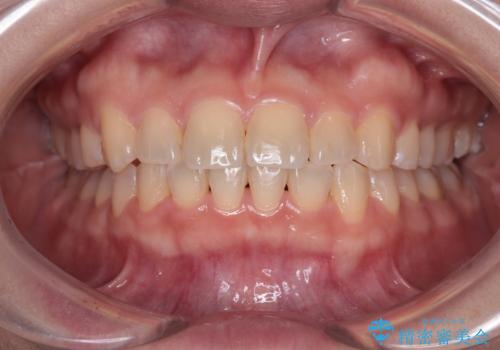

- 口元の膨らみが気になるとのことで来院された患者様です。

非抜歯で口元の突出感を少し改善させる治療も提案しましたが、最大限口元を引っ込めたいとのことでした。

上下左右第一小臼歯4本を抜歯し、ワイヤー装置により矯正治療を行うこととしました。

治療は順調に進み、予定された期間で終了することができました。

装置除去後には、スッキリとした口元となり、大変満足していただきました。